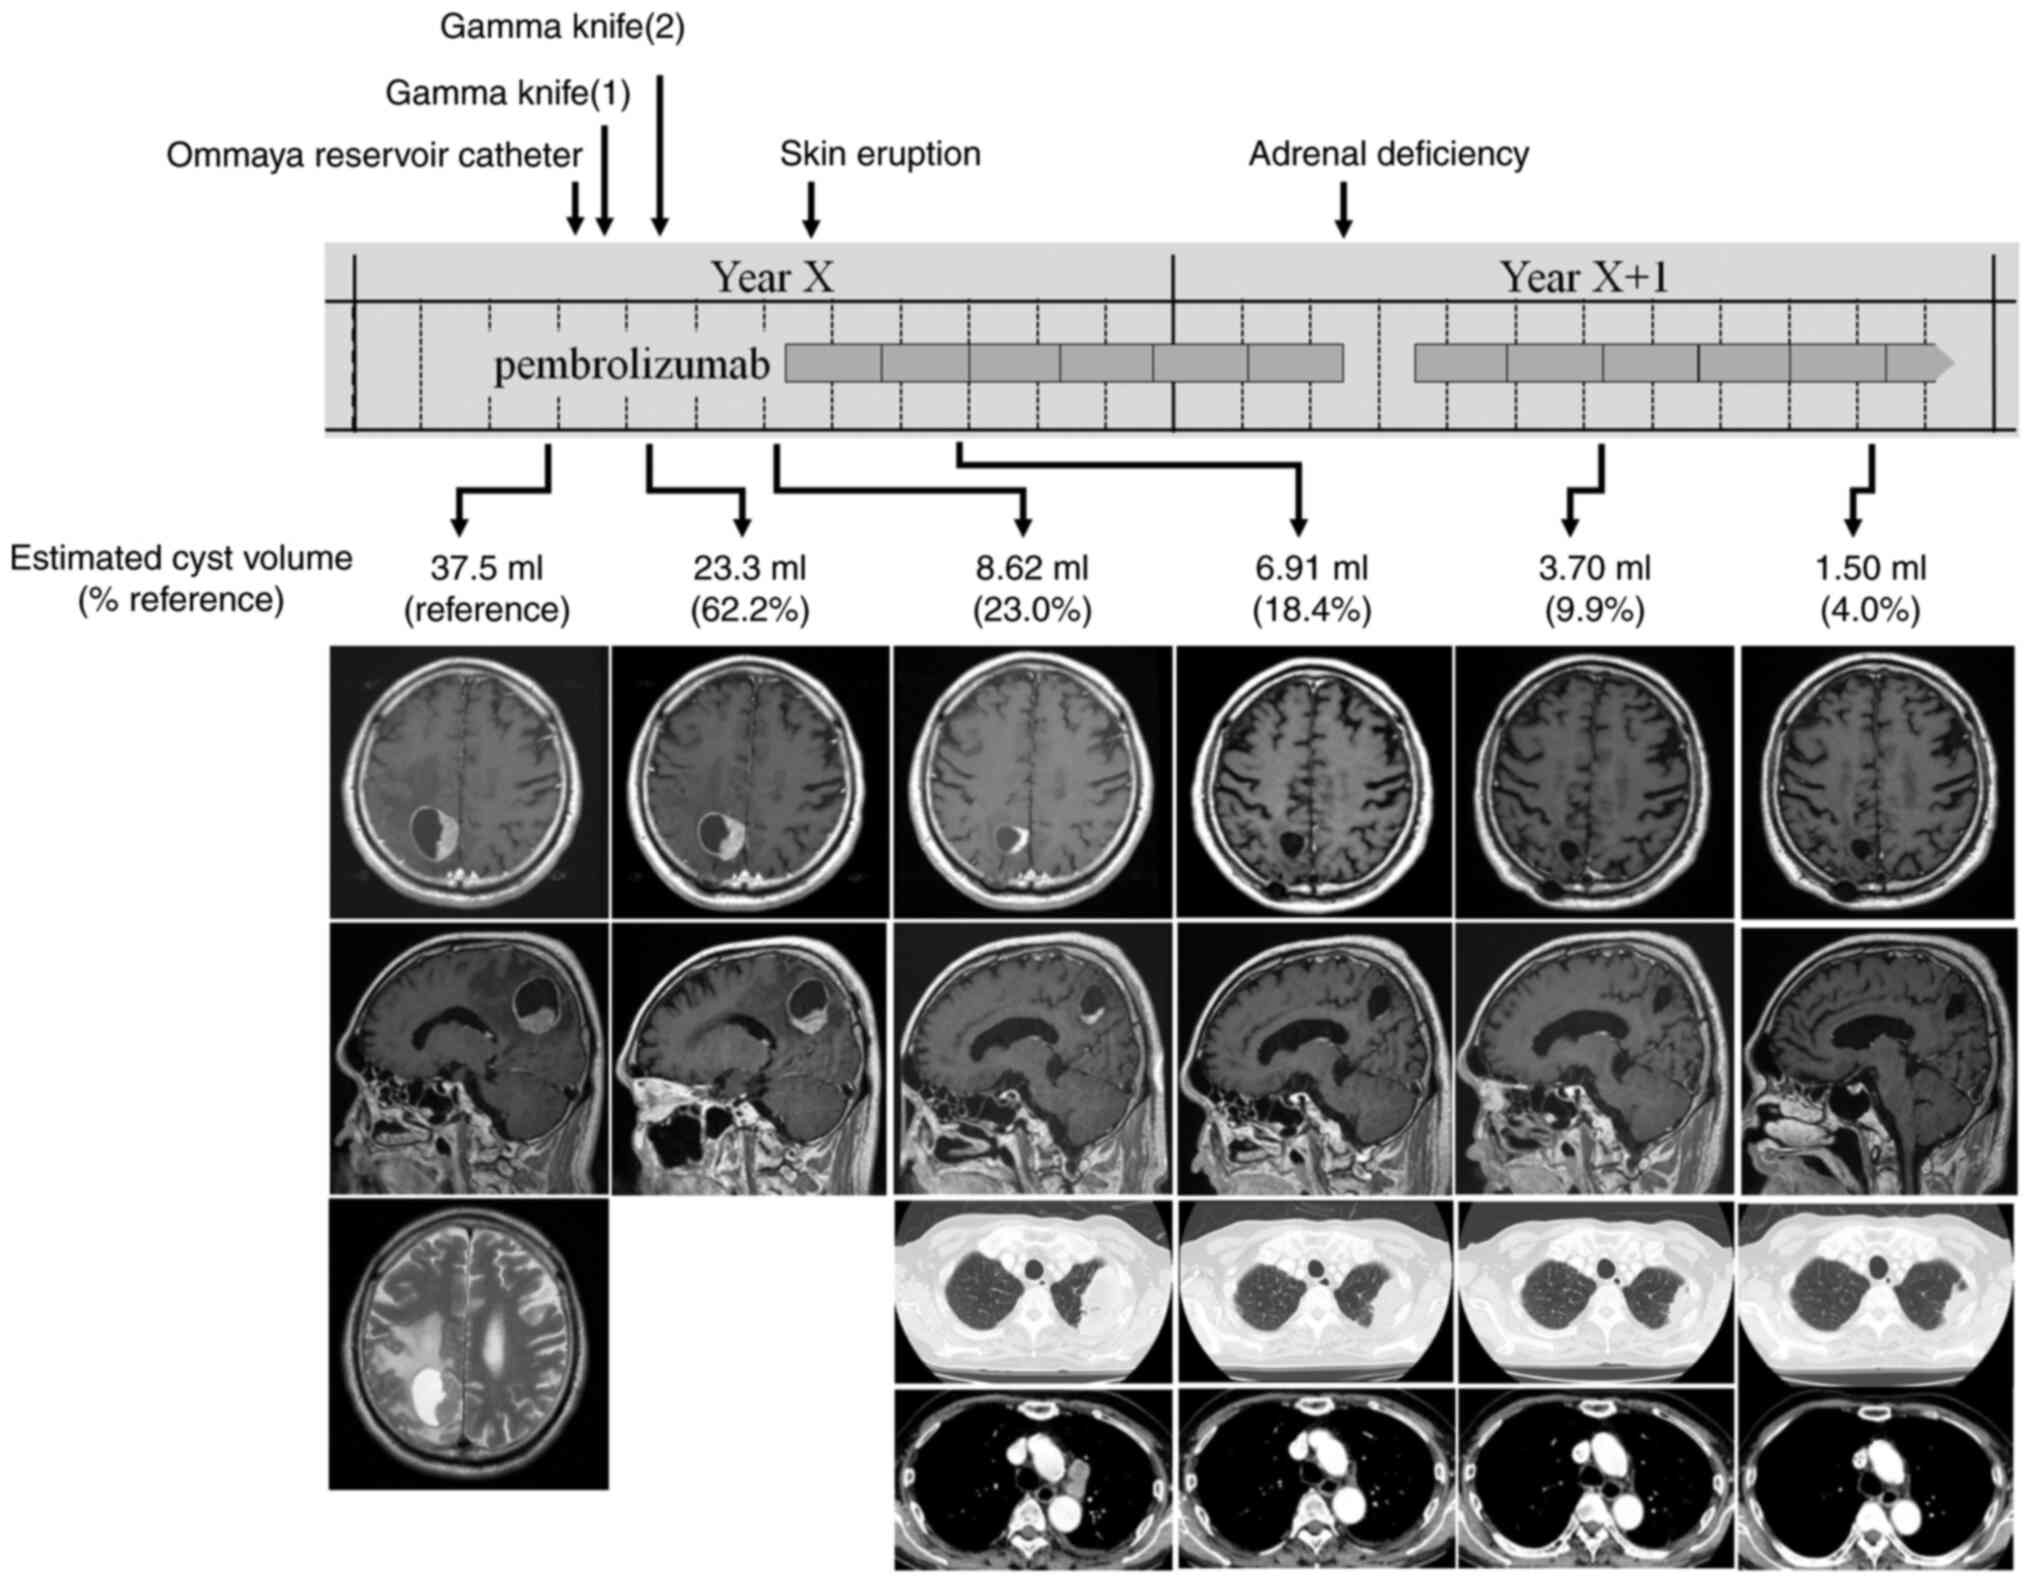

In March of Year X, the patient was admitted to Hino Municipal Hospital complaining of a walking disturbance. The patient was conscious, and his vital signs were intact. Neurological examination revealed unilateral spatial neglect and mild hemiparesis of the left extremities. Chest radiography and computed tomography revealed a primary lung tumor (maximum diameter, 60 mm) invading the chest wall in the left upper lobe and subaortic lymphadenopathy (Fig. 2A-C) without any other metastatic sites. Gadolinium-enhanced magnetic resonance imaging showed a solitary brain tumor in the right parietal lobe (maximum diameter, 40 mm) consisting of solid and cystic components (estimated cyst volume, 37.5 ml) (Fig. 3, reference group). A retrospective review of imaging examinations revealed that the lung tumor was 20 mm in diameter, and brain metastasis was absent 1 year ago. Cyst aspiration of the BM followed by surgical resection or stereotactic irradiation was recommended for the rapid control of neurological symptoms. The patient underwent placement of an Ommaya reservoir catheter, and 7 ml of bloody-yellowish aspirate was collected, in which cohesive pleomorphic malignant cells were detected. Unfortunately, the catheter collapsed early, resulting in insufficient tumor shrinkage. While catheter replacement or surgical resection of the BM were treatment options, split gamma knife (GK) was performed to minimize the patient's therapeutic burden and allow an earlier initiation of immunotherapy. A twice-split GK was performed with a prescription dose to tumor margin of 14 Gy each, resulting in a shrinkage of the solid portion and reduction in cyst volume by 62.2 and 23.0% following the first and second rounds of GK, respectively (Fig. 3). During the period of GK treatment, the patient's neurological symptoms improved to the point where he was able to walk independently and was discharged from the hospital. In July of Year X, the patient started anti-PD-1 immunotherapy (pembrolizumab, 400 mg intravenous administration, every 6 weeks). After two cycles of treatment, substantial regression was observed in the primary tumor and a mediastinal lymph node, thereby indicating a partial response (Fig. 3). In addition, the solitary compartment of the brain metastasis disappeared, and the cyst volume further decreased by 18.4% during this period. Skin eruption and adrenal deficiency appeared after the first and sixth cycles of pembrolizumab treatment, respectively, and were treated appropriately. The patient is currently continuing pembrolizumab for 12 cycles and has maintained progression-free survival. The patient did not complain of any neurological or physical symptoms.

Figure 3.

A schematic presentation of the clinical course. The treatment and clinical events are shown at the top. T1 images of gadolinium-enhanced MRI of the brain are chronologically displayed in the middle. A T2 image of brain MRI (reference group) and contrast medium-enhanced computed tomography images of the chest (other groups) are shown at the bottom. Estimated cyst volumes and a solid portion of brain metastasis were reduced with the gamma knife treatment. The primary lung tumor and brain metastasis regressed following subsequent immunotherapy using pembrolizumab. MRI, magnetic resonance imaging.